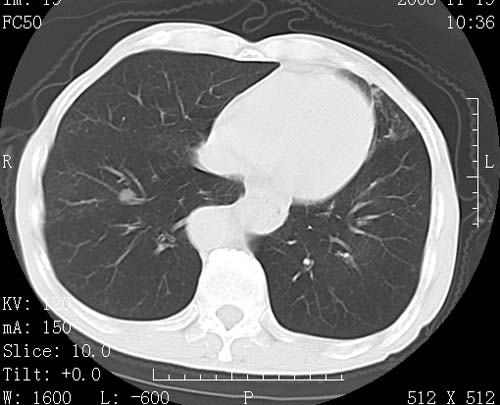

术前查体,双肺部结节是转移?结核?请点评

1)符合食管癌表现。2)两肺及纵隔淋巴结多发性转移瘤。3)左肺上叶舌段及两肺下叶炎症感染。

1)符合食管癌表现。2)两肺及纵隔淋巴结多发性转移瘤。3)左肺上叶舌段支气管扩张伴感染.

食管癌伴双肺转移,评述:肺部毛细血管网丰富,全身血液均快速流经肺部,癌细胞容易过滤定植,形成转移瘤,影象特点为以毛细血管末梢为中心的结节灶,边缘光滑锐利,少见有中心空洞着,不同来源的转移瘤可有各自特点,如甲状腺癌为双肺弥漫性微结节,本例有原发灶,双肺影象灶典型,左肺舌段条带状网格样伴胸膜天幕征,可视为癌性淋巴管炎。

左肺舌段有斑点钙化灶,能否说明是结核而不是转移?如果是转移将放弃手术改成化疗,如果是结核将考虑择期手术